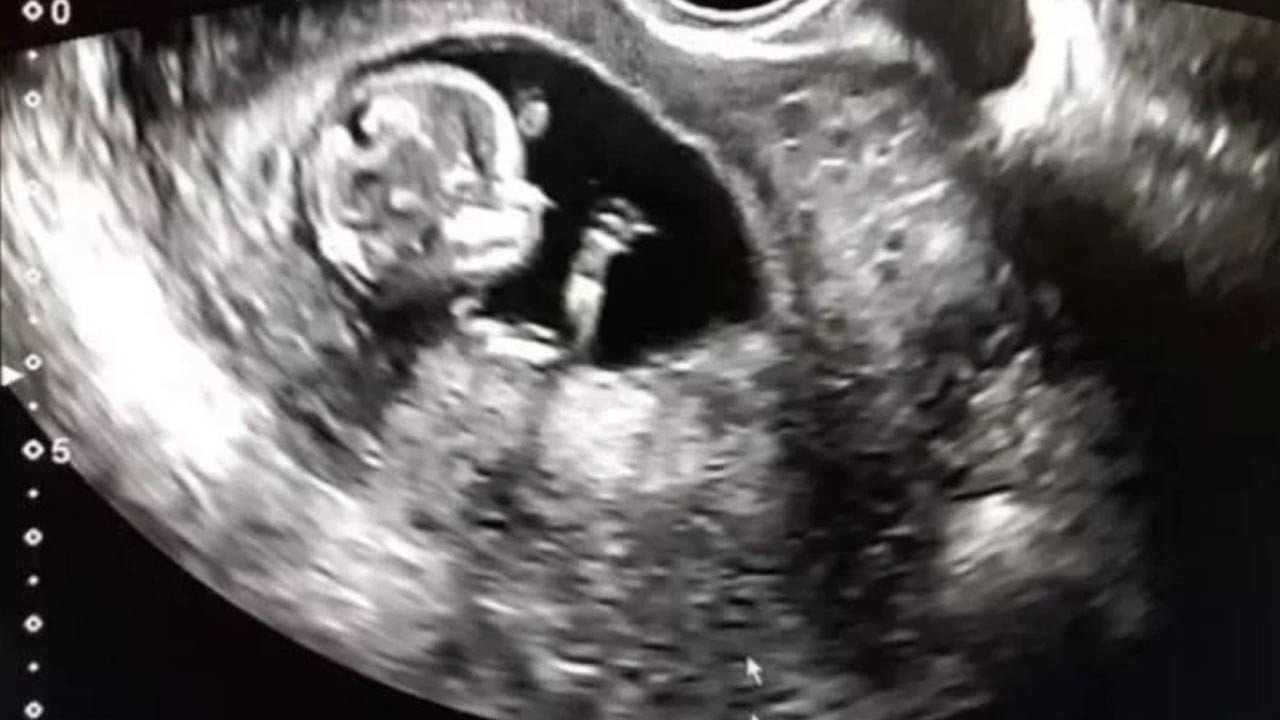

İran'da 30 milyonda bir görülen olayda bir bebek cinsel organı olmadan doğdu.

İran'da dünyaya gelen bebek hem doktorlara hem de ailesine büyük bir şaşkınlık yarattı. Cinsel organı olmadan doğan bebeği duyan şaştı kaldı. Bu olay dünyada 30 milyonda bir görülüyor. Cinsel organı olmadan doğan bebek hakkında büyük bir tartışma da var...

Bebeğin annesi yaptığı açıklamada gayet normal bir hamilelik geçirdiğini söyledi. Bebek iki testisi olmasına rağmen penis veya vajinaya sahip olmadan doğdu. Cinsel organı olmadan doğma vakalarının oldukça nadir olarak 30 milyonda bir görüldüğünü belirten doktorlar bebeğe organ yapacaklarını açıkladı. Aphallia adı verilen bu durumun tıbbi literatürde 100'den az vaka belgelendiğini söylendi.

Bebeğin idrarını nasıl yapacağı merak konusu olmuşken anüsünden yaptığı açıklandı. Aphallia, hamileliğin ilk birkaç ayında genital organların rahimde normal şekilde gelişmemesi durumunda ortaya çıkar. Erkeklerin iki penisle doğduğu, diphaliye neden olan benzer bir süreçtir. Radyoloji Vaka Raporları dergisinde vakayı bildiren sağlık görevlileri , çocuğun normal olarak "iyi bir genel durumda" doğduğunu söyledi.

Günümüzde cerrahlar, falloplasti olarak bilinen bir prosedürle, aphallia ile doğan erkek çocukları için yapay penis yapabiliyor. Doktorların üriner sistemlerini tekrar birbirine bağlamasıyla onlara bir üretra da verilebilir. Ancak bu durumda, sağlık görevlileri tartışmalı bir şekilde önerilen tedavinin cinsiyet değiştirme ve sahte vajina oluşturmak için kadınlaştırma ameliyatı olduğunu söyledi. Ayrıca, yeni cinsiyetine uyum sağlamak için yüzdeki kılların gelişmesi ve sesin kalınlaşması gibi vücudundaki değişiklikleri bastırmak için ergenlik döneminde östrojen tedavisini de önerirler.